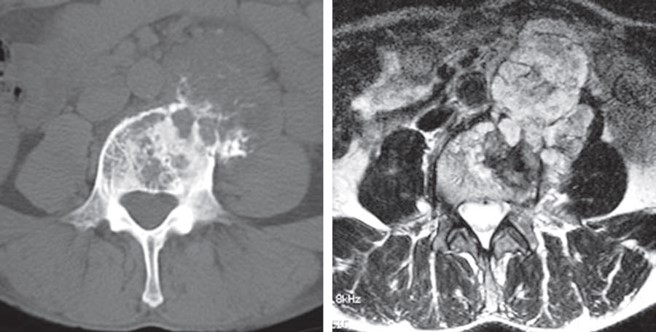

骨肉腫

• CT、T2WI

軟骨肉腫